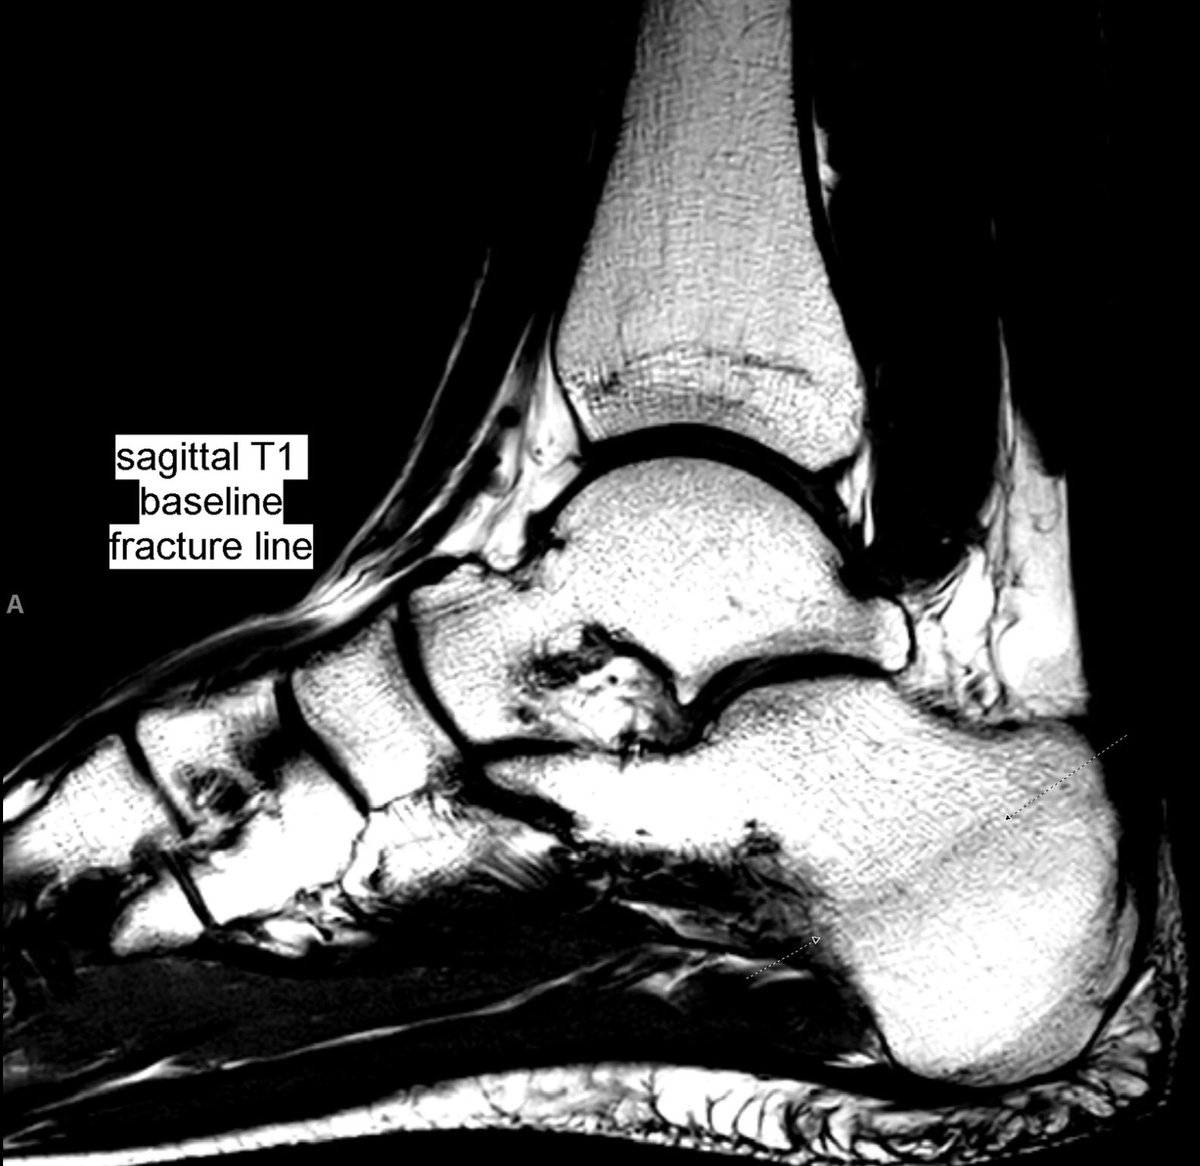

Pain worsening after rest. New MRI 18 days after to rule out again stress fracture, now clearly seen. Back to baseline examination, the oblique fracture plane was better seen as a subtle line in sagittal images.

#peerlearning#MSKrad#foot#orthopaedicspic.twitter.com/HtDYoFvH8V